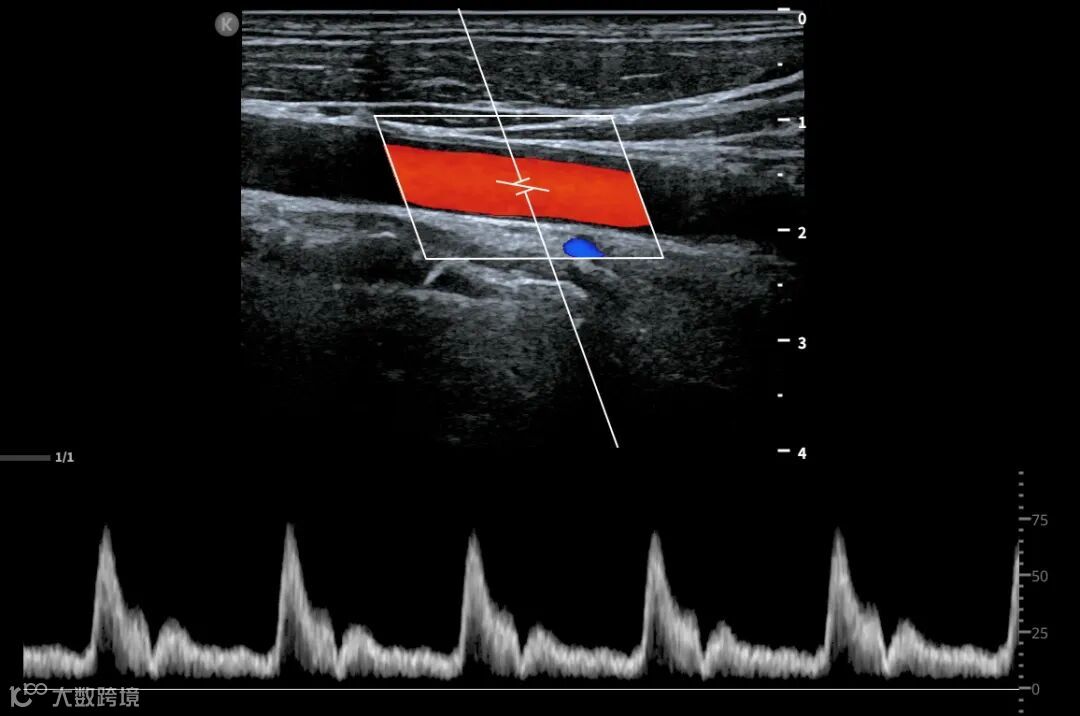

深圳鲲为科技有限公司是以突破性原创技术引领,并致力于下一代超分辨超声开发的专业影像设备公司。